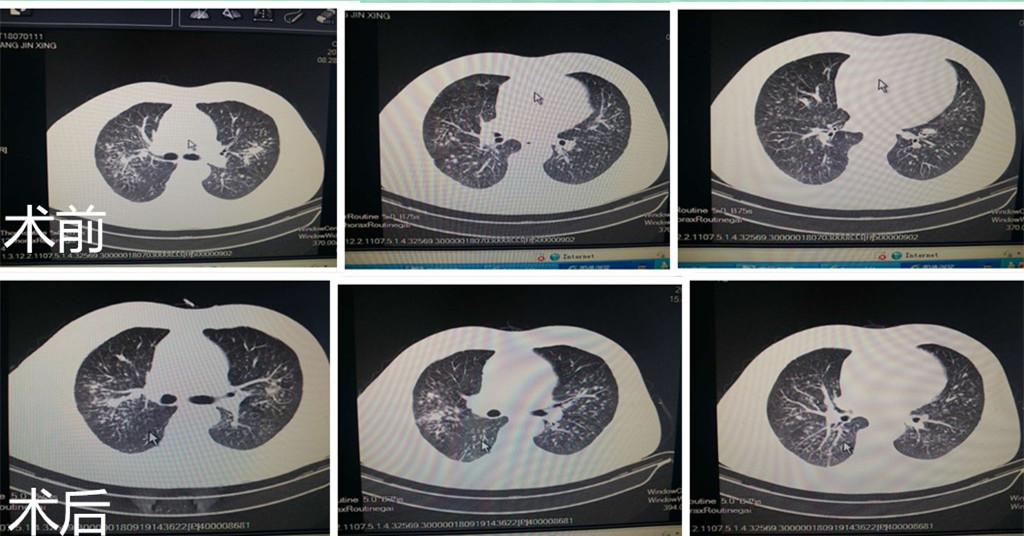

典型病例介紹:患者男性,55歲,因“反復咳嗽、胸悶5年,加重10天”入院?;颊?年前受涼后出現咳嗽、喘息,咳灰色稀薄痰,上述癥狀反復出現,多以受涼后誘發(fā),藥物治療效果差,煤礦工人,井下工作約35年,2014年診斷為“塵肺病”,入院查體: T 36.4℃,P 74次/分,R 18次/分,BP 120/80mmHg,雙肺呼吸音低,聞及細濕羅音,兩肺彌漫結節灶,提示塵肺病,入院后給予在手術(shù)室全麻成功后行全肺灌洗術(shù),灌出液體逐漸由渾濁變清。手術(shù)順利,術(shù)后復查血氣未見(jiàn)異常,生命體征平穩,安返病房。術(shù)后患者自覺(jué)胸悶癥狀明顯好轉,復查胸部CT可見(jiàn)雙肺病灶明顯好轉。